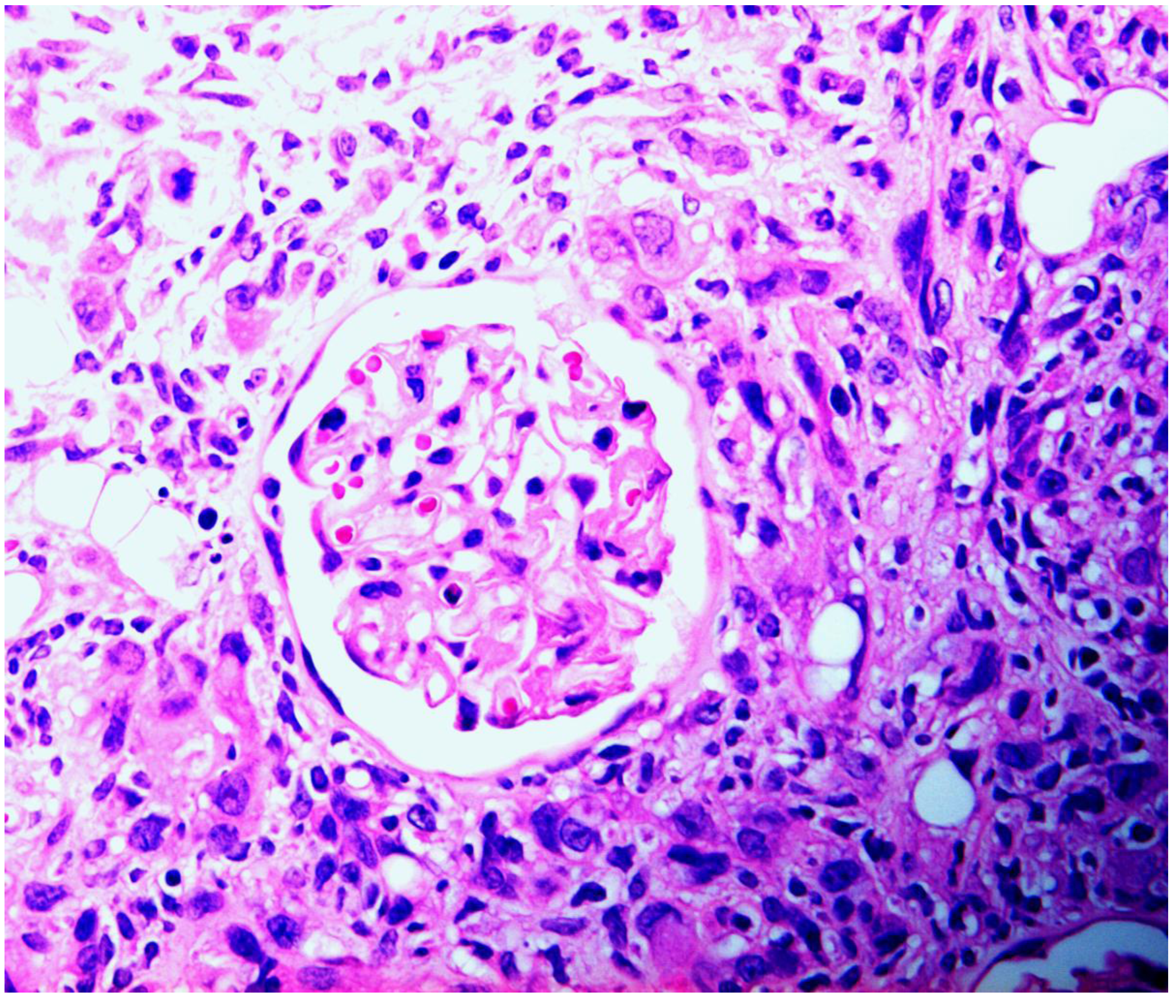

Figure 4.

Rat renal carcinoma, characterized by disorganized proliferation of cells with pleomorphic nuclei, infiltrating (left) into cortex and enveloping an intact glomerulus.

The present situation with respect to nephrotoxicity of P. polonicum has echoes of a mycotoxicosis caused by Fusarium verticilliodes, described in its first report [29] as hepatocarcinoma and oesophageal basal cell hyperplasia in rats fed an artificially moulded dietary component. The finding generated wide interest, particularly in the USA, because the fungus readily causes spoilage of maize. There was also a regional hypothesis concerning putative involvement in hotspots of human oesophageal cancer in the Republic of Transkei. Subsequent studies in South Africa recognised the new mycotoxin fumonisin B1 as causing diverse toxicological responses in horse (leukoencephalomalacia), pig (pulmonary oedema) and rat (renal carcinoma). For the latter, a comprehensive 2-year toxicology study has been made [30], revealing male-specific renal carcinoma. Concurrently, Hard et al. [31] stated “carcinomas induced by fumonisin B1 were predominantly a rare and highly malignant variant of renal tubule tumour capable of infiltrative growth invading between tubules and glomeruli, sequestering these pre-existent elements as entrapped remnants within the tumour mass.” Much the same could be said concerning male rat renal tumours in response to ochratoxin A, with respect to envelopment of glomeruli (Figure 4). Hard et al. [31] also recognised sarcomatoid areas in the National Toxicology Program’s fumonisin renal tumours; a similar sarcomatoid component of mammary tumour has also recently been recognised in a female rat given the tumour promoter sodium barbitate in drinking water after chronic dietary exposure to ochratoxin A [32].

There is no suggestion that a karyomegalic nucleus is already en route towards renal tumourigenesis. However, demonstration of the aneuploidy in rat kidney in response to five weeks of continuous maintenance on feed contaminated with an ~20% component of shredded wheat moulded by P. polonicum has defined the extent to which the ‘polyploid’ nuclei illustrated in Figure 1 can be composed of a high proportion of incomplete genome multiples. Since the karyocytomegaly illustrated in Figure 2 persists for life [12], and aneuploid nuclei are generally recognised as having tumourigenic potential [26], the abnormal organelles may harbour genetic damage, including that resulting from mis-repaired adducts between DNA and ochratoxin A [27] or from any other putative mechanism proposed [28]. In the case of ochratoxin A, it is reasonable to consider that certain tumourigenic permutations of randomly-generated genetic change could reside in some of the karyomegalic nuclei, which are located in the rat kidney region within which renal tumours seem to arise.